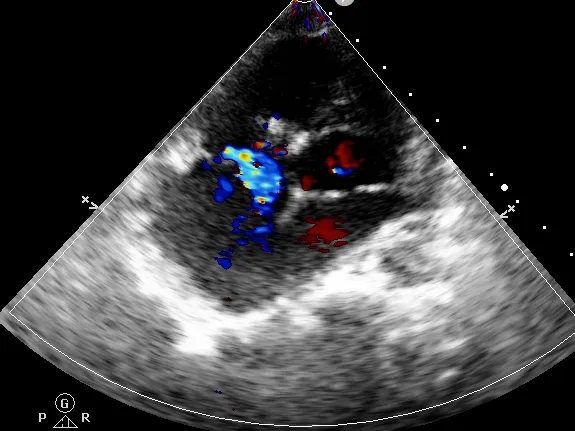

左侧伞盘出鞘为球状,牵拉成型线后形态佳,后展开右盘,封堵器呈现“长哑铃状”,主动脉瓣少量反流。

轻轻牵拉成型线使封堵器成型,牵拉后左伞盘被拉进瘤腔内。

左右盘展开后,封堵器未锁定时造影可见封堵器中间少量反流,主动脉瓣少量反流。

牵拉成型线锁定后,分流消失,主动脉瓣反流消失。

封堵器锁定后呈“蝴蝶状”明显盘状形态,室水平分流完全消失,主动脉瓣反流消失。

大动脉短轴切面,封堵器释放后双盘紧贴间隔,呈现完美“工字形蝴蝶形”,顺应VSD形态及瓣膜形态。

MemoSorb全降解VSD封堵器展现了极佳的顺应性,在通过长隧道、小出口的VSD后,能顺利从“长哑铃”形态展开并固定为贴壁良好的“蝴蝶”形态。术后即刻超声评估显示,伞盘封堵完全,对相邻瓣膜无任何影响,主动脉瓣及三尖瓣均未出现反流。